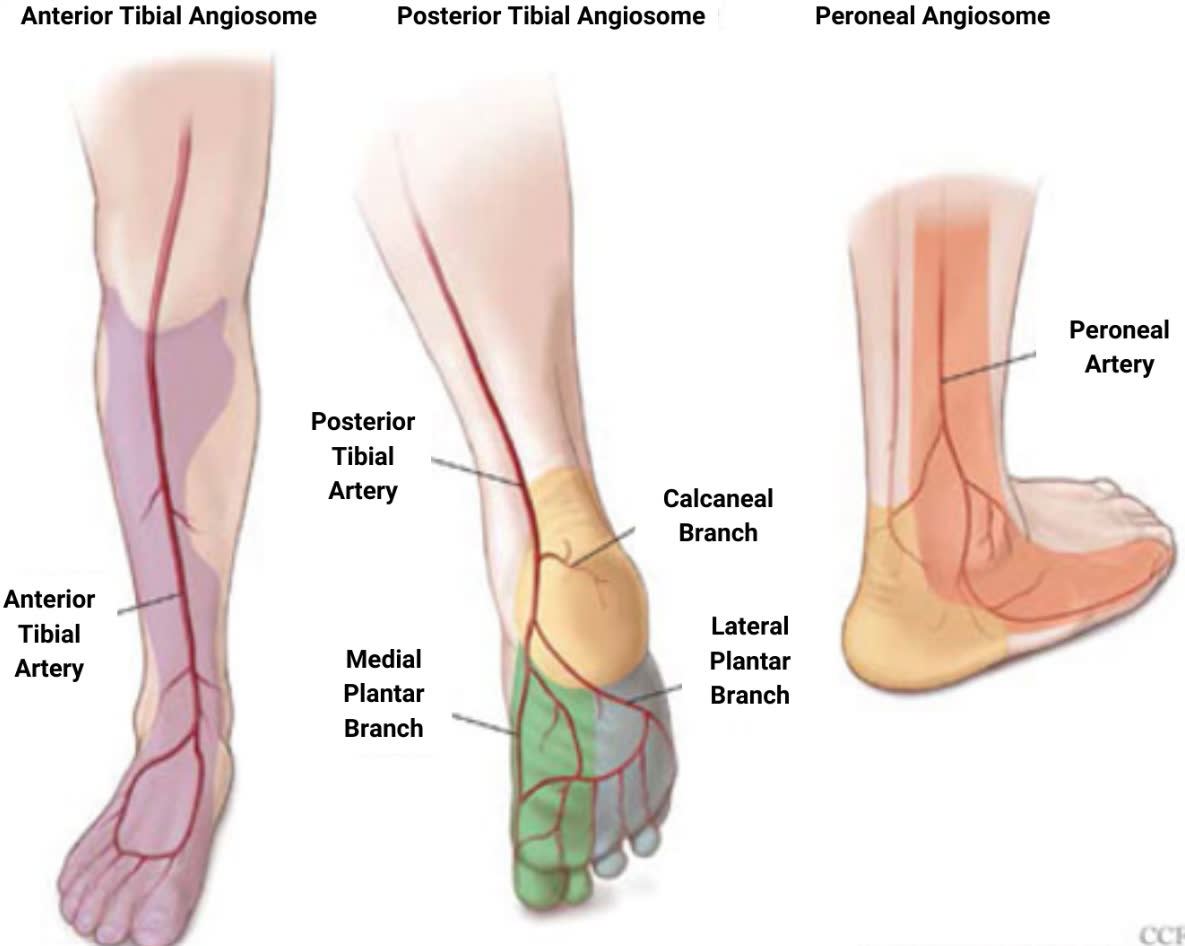

Кровоснабжение и ангиосомы

Дистальный отдел голени кровоснабжается тремя основными артериями, каждая из которых формирует свой ангиосом:

- Передняя большеберцовая артерия — передняя поверхность голеностопного сустава, тыл стопы. Проходит в переднем компартменте между передней большеберцовой мышцей и длинным разгибателем пальцев, затем переходит на тыл стопы как тыльная артерия стопы

- Задняя большеберцовая артерия — медиальная и подошвенная поверхность. Проходит в глубоком заднем компартменте позади медиальной лодыжки

- Малоберцовая артерия — латеральная и задняя поверхность. Конечные ветви (прободающая передняя, латеральная пяточная) кровоснабжают латеральную область голеностопного сустава

Между ангиосомами располагаются «водоразделы» (watershed zones) — зоны двойного кровоснабжения из смежных ангиосом. Параллельные разрезы, расположенные в пределах одного ангиосома, безопаснее, чем разрезы, пересекающие ангиосомные границы.

Передняя поверхность большеберцовой кости — наиболее уязвимая зона из-за минимального мышечного покрытия и конечных ветвей кровоснабжения.

Топография хирургических коридоров

Переднелатеральный коридор (по латеральному краю длинного разгибателя пальцев и передним краем малоберцовой кости): риск повреждения поверхностного малоберцового нерва, который расположен в поверхностном слое до фасции голени. Сосудисто-нервный пучок (a. tibialis anterior, n. peroneus profundus) располагается в глубоком слое, на уровне голеностопного сустава, между сухожилием длинного сгибателя первого пальца и длинным сгибателем пальцев.

Переднемедиальный коридор (между сухожилием передней большеберцовой мышцы и медиальной лодыжкой): должна выполняться минимальная диссекция мягких тканей. Риск повреждения v. saphena magna и n. saphenus, располагающихся впереди медиальной лодыжки в поверхностном слое.

Заднелатеральный коридор (между малоберцовыми мышцами и длинным сгибателем большого пальца): безопасная зона при условии работы латеральнее длинного сгибателя первого пальца (FHL). Риск — n. suralis при мобилизации малоберцовых мышц. Глубокий сосудисто-нервный пучок (a. tibialis posterior, n. tibialis) располагается медиальнее сухожилия длинного сгибателя первого пальца.

Заднемедиальный коридор (между задней большеберцовой мышцей и длинным сгибателем пальцев): обеспечивает доступ к заднемедиальным фрагментам и тарзальному каналу. Риск — задний сосудисто-нервный пучок располагается латеральнее этого интервала.